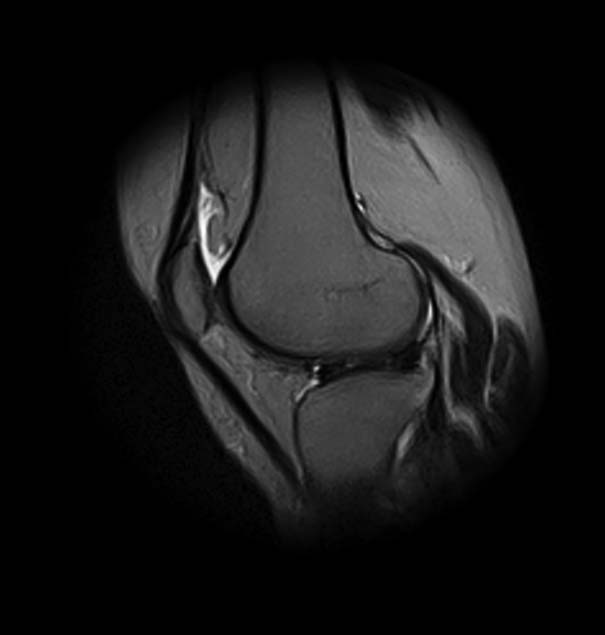

Женщина 45 лет, в течение 5 лет отмечает боли в передне-наружном отделе левого коленного сустава, при повороте туловища и фиксированной стопе, а также при спуске по лестнице боли усиливаются. Клинически - болезненность в проекции переднего рога и тела латерального мениска. Но меня смущает МРТ - нет ли кистозного перерождения и кисты мениска?

добрый день! Не очень понятен принцип, по которому отбирались снимки МРТ. Большинство из них не показательны. Вижу пока только повреждение хряща на феморопателлярной поверхности. Хлтелось бы посмотреть диск целиком

На снимках повреждений наружного мениска не вижу и кисты мениска не вижу. Есть повреждение хряща на передней поверхности внутреннего мыщелка бедра. Вполне может оказаться, что повреждение лоскутное. А какая консервативная терапия проводилась?